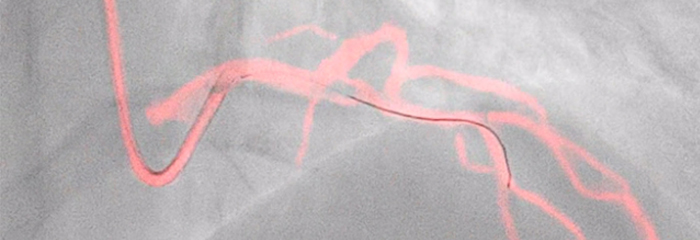

Visualización clara, orientación fiable: Dynamic Coronary Roadmap

Orientación de navegación automática en tiempo real diseñada para la eficacia del procedimiento en intervenciones complejas de ICP sin afectar al flujo de trabajo estándar actual.You are about to visit a Philips global content page

Cociente instantáneo de presión libre de ondas: iFR

El índice fisiológico sin hiperemia líder para medir la presión en procedimientos diagnósticos e intervencionistas, que puede mejorar los resultados, ahorrar tiempo y reducir las molestias para el paciente. iFR se mide con el primer cable guía de presión de núcleo sólido del mundo, OmniWire, con valores reposicionados* directamente en la angiografía. Esta orientación fisiológica avanzada ayuda a identificar con precisión qué partes de un vaso están causando isquemia, lo que facilita la elección del tratamiento.

* Disponible con IntraSight 7 y SyncVisionYou are about to visit a Philips global content page